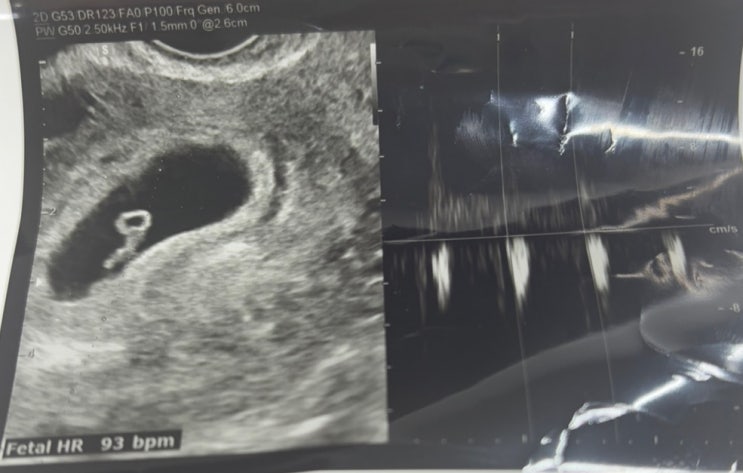

임신 6~7주차, 낮은 심박수로 피말리던 시간

아기집을 확인하고 일주일 뒤, 엄마와 함께 산부인과를 방문했다. 첫 심장박동 소리를 듣는 감격스러운 순...